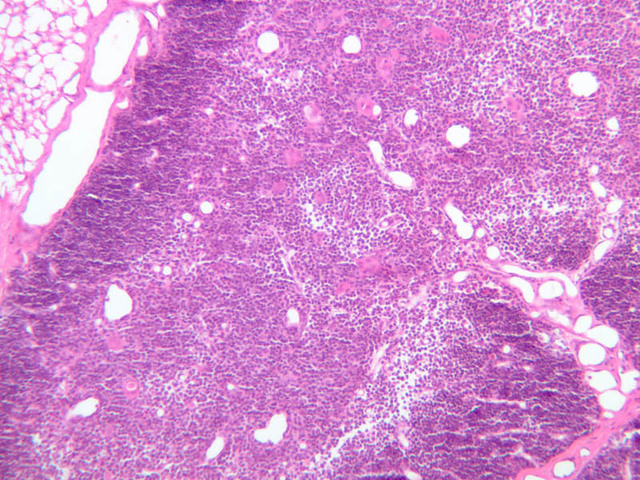

Sections through the spleen (slides A-36, aniline blue [2.5x, 10x, 20x-labeled, 40x] [2.5x, 10x-labeled, 20x-labeled, 40x]; A-37, retic [2.5x, 10x, 20x-labeled, 40x]; A- 37, H&E [2.5x-labeled, 10x, 20x, 40x]; A-38, H&E [10x, 20x, 40x]; A-39, H&E [2.5x, 10x, 20x, 40x]) show a thick investing capsule composed of collagenous tissue and smooth muscle, typically covered with mesothelium. In slide A-36 muscle and collagen are brightly stained. The capsule and mesothelium completely surround the organ and the fibrous portion enters the splenic substance at the hilus around the splenic arteries and veins forming trabeculae of fibromuscular tissue within the splenic substance. This fibromuscular tissue enables the spleen to expel blood by contracting. Identify trabeculae as fibrous partitions in the section and look for blood vessels within them.

Where the trabecular arteries pass into the splenic pulp, they become invested by a sleeve of lymphoid tissue. This lymphatic tissue collectively forms the white pulp of the spleen (A-36 [2.5x, 10x, 20x, 40x]). It also is referred to as the periarterial lymphatic sheath or PALS. On an H&E stained section (A-38 [2.5x, 10x, 20x, 40x] [2.5x, 10x, 20x, 40x]) the white pulp will appear as basophilic clumps of lymphoid cells. The arteries of the white pulp are called central arteries, although they may be displaced to one side of the lymphoid sleeve by the presence of a nodule. The majority of cells forming the PALS are T lymphocytes. In places the covering of lymphatic tissue is enlarged due to the presence of lymphoid nodules (splenic or Malphighian corpuscles) which are comprised predominantly of B lymphocytes.

The remainder of the cellular mass in the spleen is red pulp (A-38 [10x, 20x, 40x]), made up of red and white cells of the blood enmeshed in the reticular tissue of splenic cords and present in the splenic sinuses. After passing through the PALS, the trabecular arteries branch to form smaller arterial vessels known as penicillar arterioles which narrow, forming arterial capillaries that empty into the cords of the red pulp (open circulation) or into the venous sinuses (closed circulation). In the splenic sinuses the cells of the blood are exposed to red pulp macrophages. The splenic sinuses eventually become confluent to form veins that enter the trabeculae and gradually merge meeting in the hilus to form splenic veins.

Examine the composition of the red pulp tissue. The three dimensional structure of the red pulp is analogous to Swiss cheese with the holes being the venous sinuses and the cheese being the parenchyma (i.e. splenic cords). On slide A-36 which is stained with Mallory's aniline blue locate examples of the splenic sinuses ([2.5x, 10x, 20x, 40x-labeled] [10x, 20x, 40x]). The walls of the splenic sinuses consist of adjoining specialized endothelial cells whose nuclei in many cases stand out from the wall in a bead-like fashion. The basement membrane of the epithelial cells stains blue revealing the sinuses quite nicely. Usually the sinus lumen is filled with red cells and leukocytes. The skeletal framework of the cords is provided by a network of reticular fibers. As above, the reticular cells are best seen using a reticular fiber stain (slide A-37 [2.5x, 10x, 20x, 40x-labeled]). Look for the large pale nuclei of reticular cells that have darkly stained reticular fibers. Fibers run irregularly in the cords, but clearly outline the sinuses around which they are wrapped. Notice on this same slide that there is much less reticular tissue in the white pulp than the red. The splenic cords occur around the sinuses and are distinguished by the presence of disintegrating red blood cells undergoing phagocytosis.